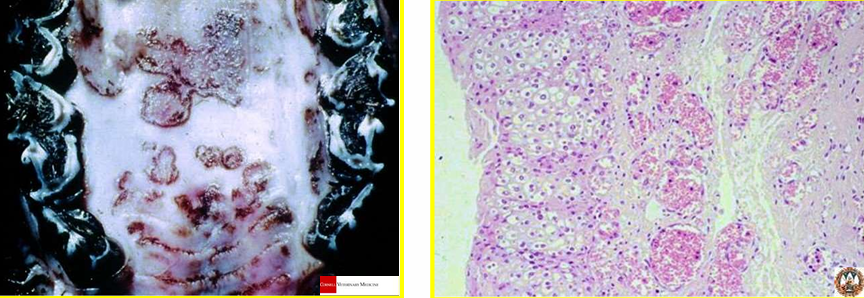

ECTIMA CONTAGIOSO = Estomatitis papular

elevado, proliferación epitelial + degeneracion hidrópica epitelial

x poxvirus = cuerpos de inclusión intracitoplasmáticos

ESTOMATITIS PAPULAR BOVINA